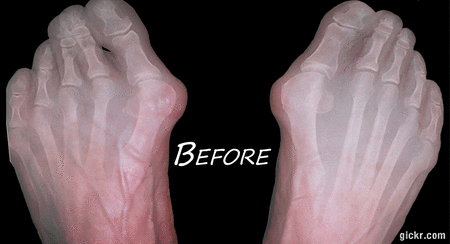

¿Sufres de dolorosos juanetes o fascitis plantar? No estás solo, y no tienes que seguir soportando esas molestias. Nuestro Corrector de Pies está diseñado para ayudarte. Pensado para apoyar y fortalecer tus pies, actúa directamente sobre la causa del dolor para que puedas moverte con más facilidad, comodidad y confianza. No solo manejes el dolor, ¡empieza a corregirlo!

Nuestro Corrector de Pies está diseñado cuidadosamente para ayudar a corregir problemas comunes en los pies, como juanetes, pies planos, fascitis plantar y más. Si sufres de molestias, desalineación o debilidad, esta herramienta te ayudará a reentrenar tus pies para que se muevan y funcionen como deberían.

1. Juanetes

2. Pies planos

3. Fascitis plantar

4. Deformidades en los dedos

Si estás sufriendo de estas condiciones, usar un corrector de pies desde temprano puede ayudar a prevenir daños mayores y reducir el riesgo de complicaciones más serias en el futuro. Actuar ahora significa menos dolor, mejor movilidad y una salud duradera para tus pies.